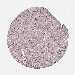

LIVER CANCER - Protein expressioni

A mouse-over function shows sample information and annotation data. Click on an image to view it in a full screen mode. Samples can be filtered based on level of antibody staining by selecting one or several of the following categories: high, medium, low and not detected. The assay and annotation is described here.

Note that samples used for immunohistochemistry by the Human Protein Atlas do not correspond to samples in the TCGA dataset.

Antibody stainingi

Antibody staining in the annotated cell types in the current human tissue is reported as not detected, low, medium, or high, based on conventional immunohistochemistry profiling in selected tissues. This score is based on the combination of the staining intensity and fraction of stained cells.

Each image is clickable and will lead to virtual microscopy that enables deeper exploration of all samples and also displays staining intensity scores, fraction scores and subcellular localization as well as patient and tissue information for each sample.

Antibody HPA050110

Antibody CAB004293

Staining

High

Medium

Low

Not detected

Intensity

Strong

Moderate

Weak

Negative

Quantity

>75%

75%-25%

<25%

None

Location

Nuclear

Cytoplasmic/membranous

Cytoplasmic/membranous,nuclear

Carcinoma, Hepatocellular, NOS

Cholangiocarcinoma